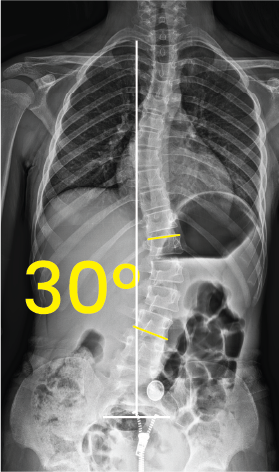

Omurga eğriliğini ve 30 derece açıyı gösteren iskeletin göğüs-karın röntgeni.Göğüs ve karın bölgesinin iki farklı açıyla çekilmiş röntgen görüntüsü ve üzerinde 8 derece açı gösteren sarı işaret.

Toraks röntgen görüntüsünde 30 derecelik skolyoz eğriliği sarı açılarla ve beyaz çizgilerle işaretlenmiş.Göğüs ve bel bölgesini gösteren röntgen, omurga eğriliğinin 14 derece olduğunu belirtir.